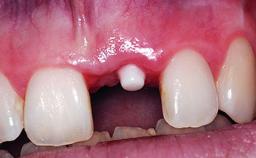

A 32-year-old female Caucasian patient with a compromised maxillary right central incisor was referred to us by a general dentist. Her chief complaints were discomfort and mobility of tooth 11 with unsatisfactory esthetics due to discoloration. The patient reported a previous trauma, some years earlier, as the origin of pathology on the afflicted tooth. Anamnesis was negative for any other dental or periodontal pathology in the remaining dentition. The patient did not take any medication and reported to be a light smoker (5–10 cigs/day). She had high esthetic expectations of her treatment. The extraoral examination revealed a high smile line with full exposure of her maxillary teeth and surrounding soft tissue in the area between the second premolars.

| Provisional Implant-Supported Prosthesis | Prosthodontic margin > 3 mm apical to mucosal margin Prosthodontic margin > 3 mm apical to mucosal margin |

| Interim Prosthesis during Healing | Fixed Fixed |